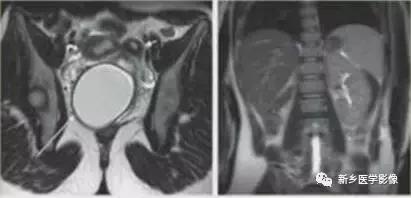

完全型纵隔子宫:宫底平坦,纵隔贯穿宫腔和宫颈

不完全型纵隔子宫:宫底平坦,纵隔未达宫颈内口水平

VI:弓形子宫

纵隔子宫:宫底轮廓凸出、平坦、轻度凹陷<1cm,肌壁或纵隔深入内膜腔>1cm。

弓形子宫:宫底轮廓凸出、平坦、轻度凹陷<1cm,肌壁或纵隔深入内膜腔<1cm。

宫底凸出、平坦、轻度凹陷(小于1cm),肌壁或纵隔深入内膜腔小于1cm.